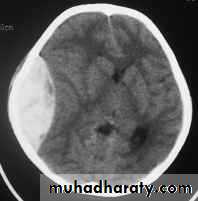

c. Intracerebral Haematoma

This is the least common of traumatic haematoma.

They are due to areas of traumatic contusion coalescing into a contusional haematoma.

Disrupted cerebral tissue release thromboplastins that potentiate haemorrhage.

CT scan: appear as hyperdence lesions with associated mass effect and midline shift.

Large intracerebral haematomas should be evacuated unless the patient’s neurological state is improving.

Small inracerebral haematomas may not require removal, but be aware that they can expand.